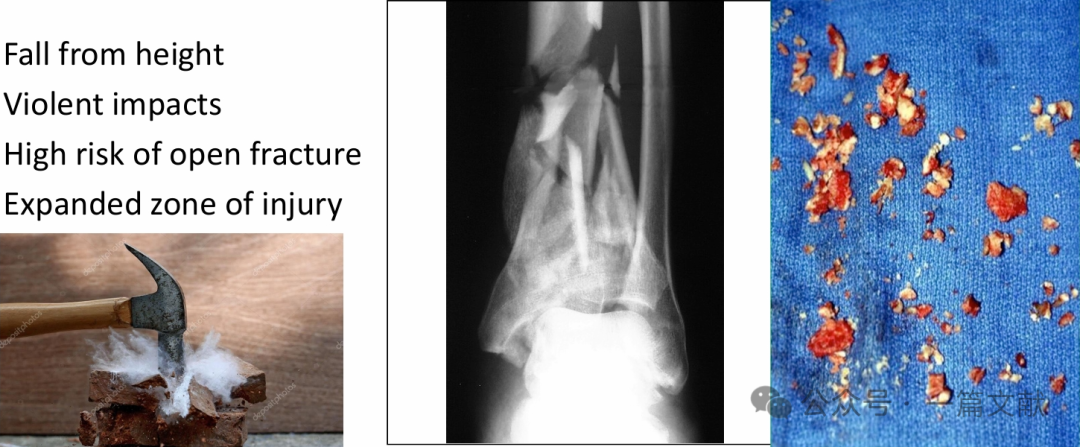

多见于高处坠落、剧烈撞击;

开放性骨折概率高,损伤范围广泛。